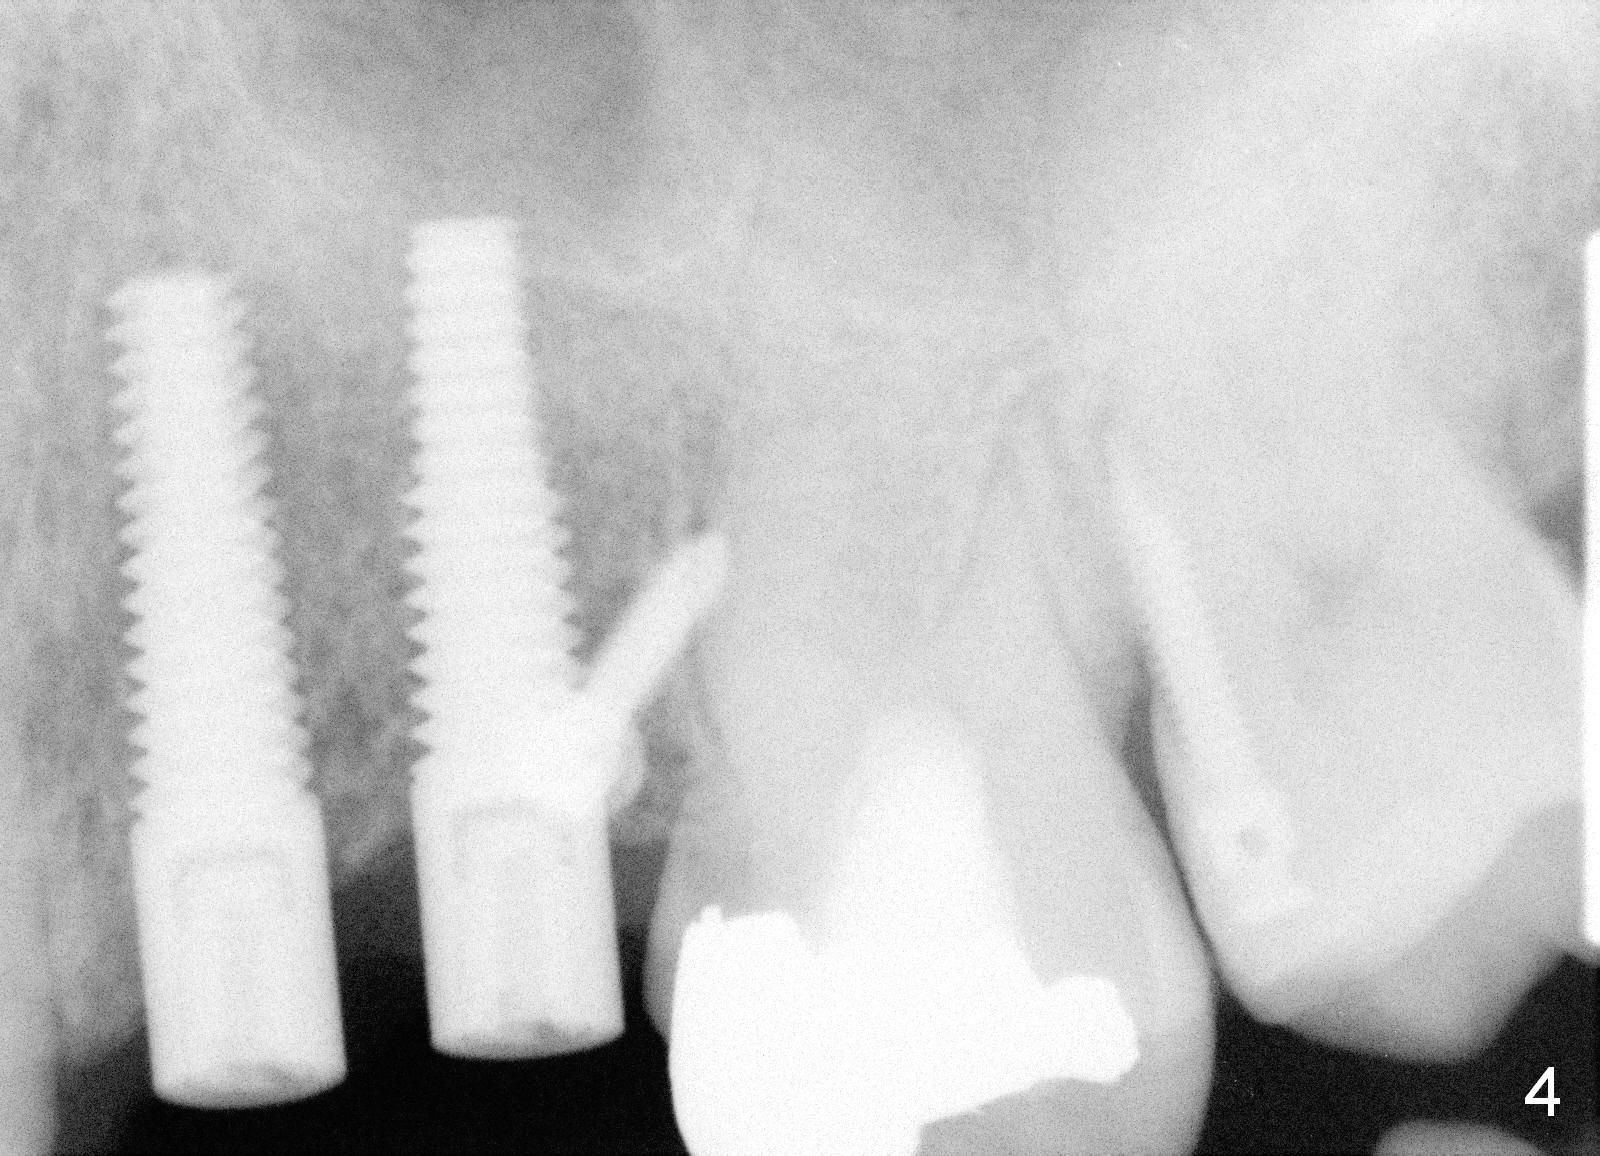

A 51-year-old man returns for #12,13 implant placement 2 years post extraction (Fig.1, 2 mm pilot drills 11 mm deep). Bone expanders are used (Fig.2 E), although the bone density is high. Two of 4x17 mm implant are placed with insertion torque > 60 Ncm (Fig.3). Four months postop, the implants are prepared for provisional as anchorage for limited ortho (Fig.4). When intrusion of #14 is finished, permanent crowns are fabricated for #12 and 13. Fig.5 is taken 1 year 1 months post cementation.